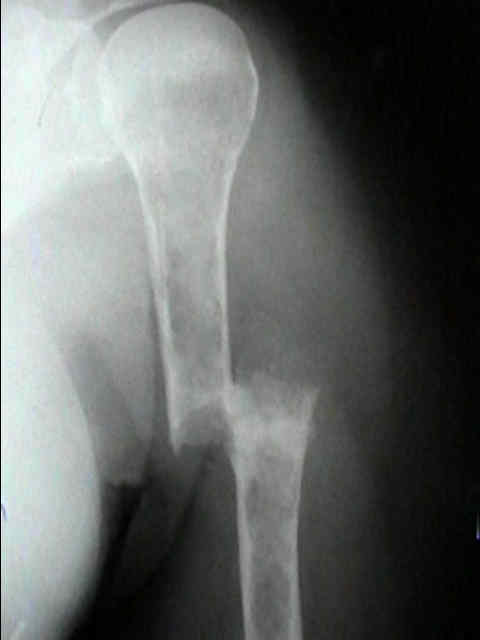

Radiographic Studies

• standard x-rays may show diffuse osteopenia

• "punched-out lesions" w/ no surrounding new-bone formation;

• over time lesions may change from diffuse osteopenia to more permeative moth-eaten destructive pattern, sometimes w/ cortical expansion;

• bone destruction occurs w/ little or no reactive bone formation unless pathologic frx is present;

• myeloma may present as solitary lesion or more commonly a diffuse tumor, involving multiple bones, including vertebrae, skull, pelvis and femurs;